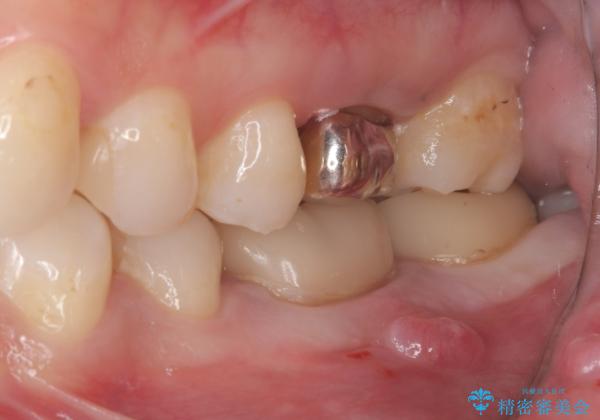

- 主訴:左下6番目の歯の周りが痛くなり、他院で診てもらったが抜歯と言われてしまった。ネットで歯牙移植というものを知りやっている医院を探している。

左下6番目の歯の周りに大きく透過像を認め、再根管治療後の予後が良くない可能性が大きく当院でも抜歯適用歯と説明しました。欠損部に対しインプラント治療や歯牙移植(左下の親知らずの移植)、ブリッジを提案し、歯牙移植を行うこととなりました。

保存が難しい左下6番目の歯を抜歯し、左下8番目の歯(親知らず)を抜歯窩に移植しました。歯牙移植後の動揺防止のため暫間固定を行っています。